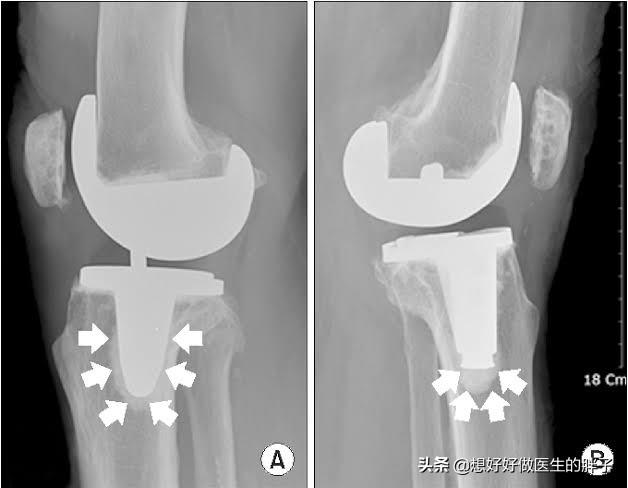

晚期骨关节炎:晚期骨关节炎由于患者已经出现了明显的关节畸形,很多患者已经谈不上生活质量,被折磨的痛不欲生,那么此时可能进行手术治疗的办法是最好的措施。过去主要采取的办法是比较单一的,我们称之为全膝关节表面置换术,也就是像膝关节软骨已经磨损殆尽的表面替换成金属表面,关节内的骨骼就不会发生直接的摩擦,疼痛也就会消失。

但是在常年的手术经验积累当中,很多医生也发现,部分患者仅仅是内侧的膝关节或者是外侧的膝关节问题比较严重,而针对某一侧的关节问题将整个关节的表面全都置换掉,确实有些可惜。所以目前也开展了单髁置换手术以及模块化的置换手术,我们统称为部分关节置换术。